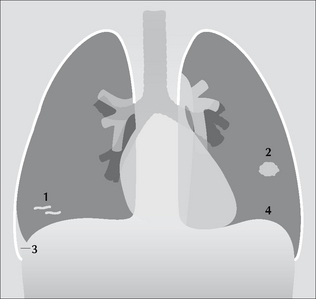

image

Figure 23.1 The CXR is frequently abnormal in PE—but the changes are usually minor12. Some of these non-specific changes are illustrated: 1 = linear areas of collapse; 2 = small area of consolidation; 3 = small pleural effusion; 4 = elevated dome of the diaphragm.